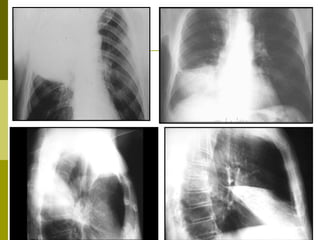

RRaaddiiooggrraapphhiiee ppuullmmoonnaaiirree

Condensation

TypiquLeS dDet …légionellose (75%)

Bronchogramme aérien

• 95.

Début brutal, crépitantssous le sein droit, Dg par hémocultures : Pneumocoque

• 97.

RRaaddiiooggrraapphhiiee ppuullmmoonnaaiirree Condensation TypiquLeS dDet …légionellose (75%)

• 98.

• 99.

SSccaannnneerr vvss rraaddiiooggrraapphhiiee TDM :Infiltrat bilatéral -LSdt, apical LIG, -pyramide basale Syrjala CID 1998